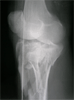

Pre

Op

Xrays

Follow

Up

X-Ray after frame removal and union

good return of knee motion soon after frame removal